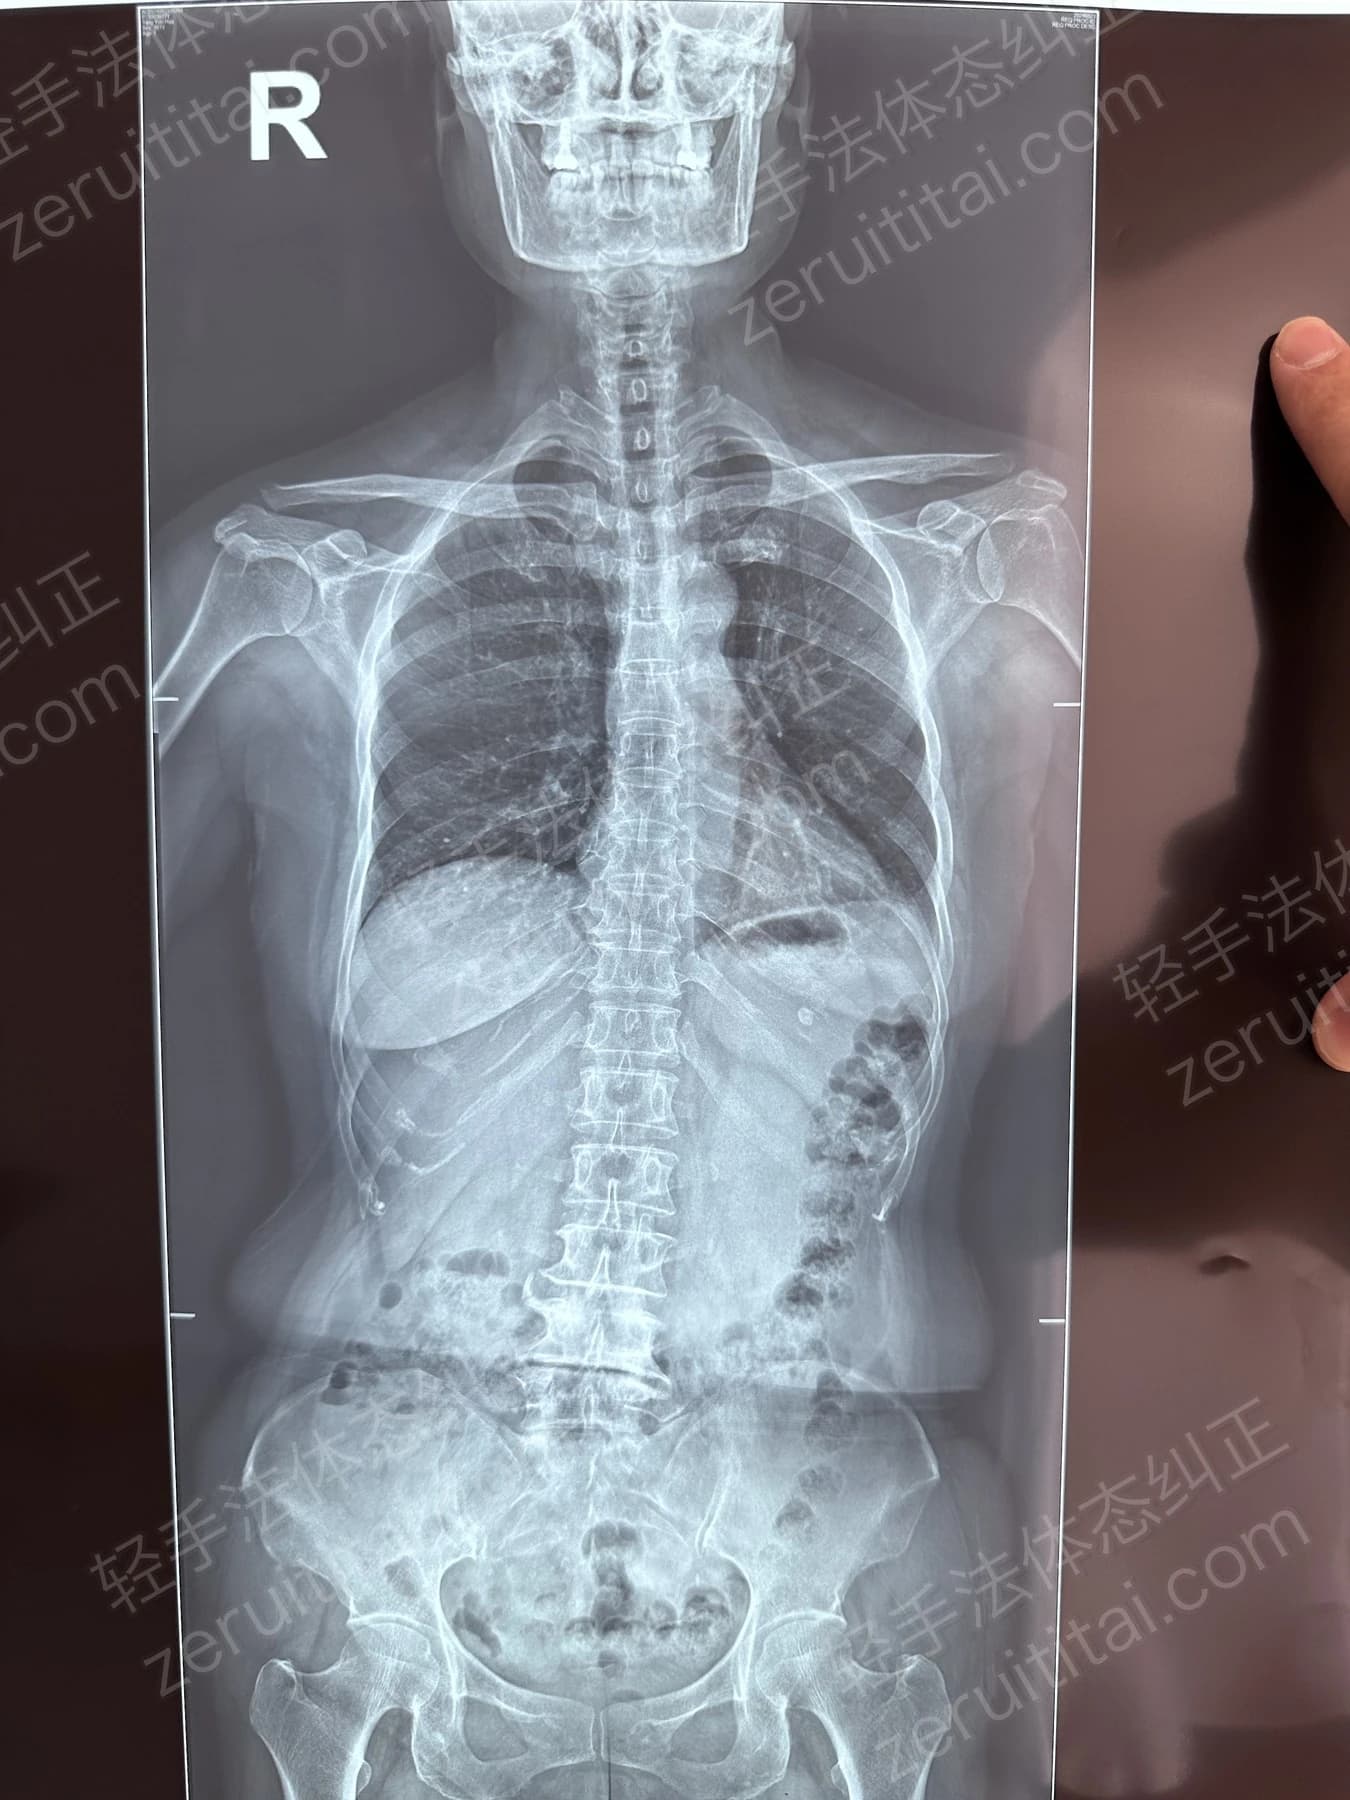

2022.06.27

第 1 次记录